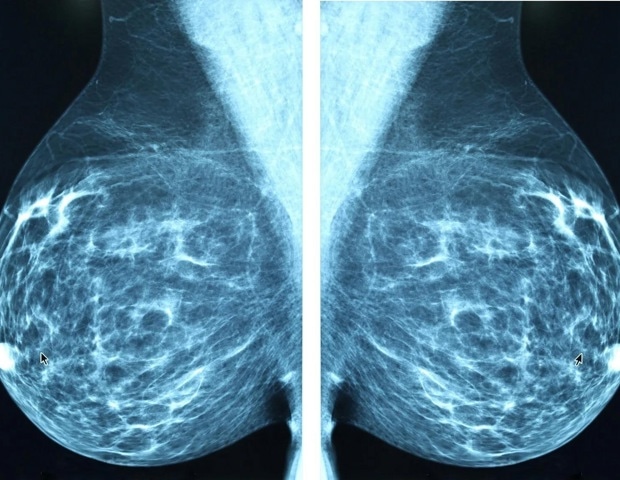

Η μαστεκτομή, αν και συχνά είναι μια απαραίτητη και σωτήρια επιλογή θεραπείας για πολλές γυναίκες με καρκίνο του μαστού, μπορεί να συμβάλλει σε αρνητικές επιπτώσεις στην σεξουαλική υγεία, την εικόνα σώματος και σε άλλες σωματικές και συναισθηματικές προκλήσεις μετά την επέμβαση. Αυτό προκύπτει από μια νέα συστηματική ανασκόπηση που εξετάζει τις επιδράσεις της μαστεκτομής σε γυναίκες με καρκίνο του μαστού. Οι χειρουργοί επισημαίνουν την ανάγκη για προετοιμασία των γυναικών πριν από τη μαστεκτομή.

Η μαστεκτομή, η οποία περιλαμβάνει την αφαίρεση ενός ή και των δύο μαστών, είναι μια σημαντική επέμβαση που απαιτεί μακροχρόνια παρακολούθηση. Περισσότερο από το ένα τέταρτο των ασθενών με καρκίνο του μαστού υποβάλλονται συνήθως σε μαστεκτομή, και πολλές παραμένουν στο νοσοκομείο για μικρότερες περιόδους μετά την επέμβαση, γεγονός που οδήγησε τους ερευνητές να αναλύσουν τα αποτελέσματα των ασθενών μέσω μιας συστηματικής ανασκόπησης. Από σχεδόν 3.000 μελέτες που εντοπίστηκαν, αναλύθηκαν 20 μελέτες που πληρούσαν τα κριτήρια ένταξης, εξετάζοντας τις επιπτώσεις της μαστεκτομής στην ποιότητα ζωής, τη σεξουαλική υγεία και την ψυχοκοινωνική ευημερία. Όλες οι μελέτες επικεντρώθηκαν στις εμπειρίες γυναικών με καρκίνο του μαστού στα στάδια 1-3.